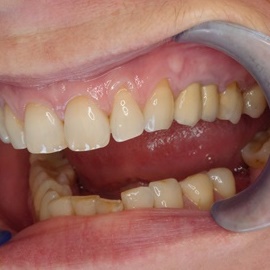

Pacjentka lat 41, odbudowa protetyczna zębów 24, 25 na implantach - korony porcelanowe na metalu. Po stronie prawej zdjęto most 13 - 16, poprawiono warunki kostne wyrostka zębodołowego i wykonano most na implantach od czwórki do szóstki, oraz nacementowano pojedynczą koronę na kła.

Pacjentka lat 50. Most od zęba 24 do zęba 27. Pękł korzeń zęba filarowego 24. Po ekstrakcji wykonano zabieg odbudowy kości wyrostka zębodołowego i podniesiono zatokę. Następnie po skorygowaniu kształtu i objętości dziąsła przytwierdzonego wykonano pojedyńcze korony na implantach 24, 26, oraz most 13-17